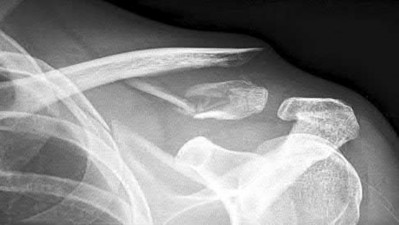

2. # A 35-year-old woman is involved in a head-on collision while driving. Initial radiographs are shown in Figures 8a and 8b. Injury to what vessel increases the risk for osteonecrosis of the injured bone?

5. Artery of the tarsal sinus Corrent answer: 4

The patient has a Hawkins type III talar neck fracture-dislocation with a risk of osteonecrosis ranging from 69% to 100%. Anatomic studies have shown that the artery of the tarsal canal supplies the lateral two thirds of the talar body.

The other vessels listed provide no significant contribution to the talus.